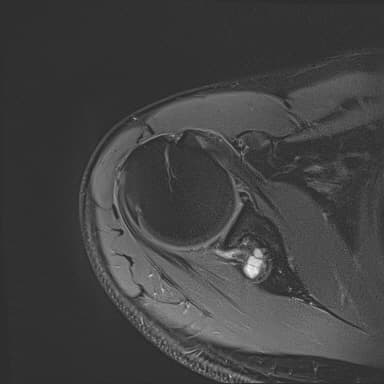

어깨 mri 좀 봐주세요 물혹있다고 하는데 수술해야 하나요?

하도 안 나아서 우측 견관절도 mri 촬영을 했는데 물혹이 있네요

이거 수술해야 하나요?

팔에 힘이 안들어간다거나 방사통이나 아파서 잠을 깬다는점등은 현재 없는데...

이거 때문에 승모근이 잘 뭉치고 목이 뻣뻣한가요?

물혹이 있다고 해서 바로 수술이 필요한 것은 아닙니다 물혹이 신경을 압박하거나 심한 통증, 마비 증상 등을 유발하지 않으면 보통 비수술적 치료로 관리가 가능합니다 승모근 뭉침과 목의 뻣뻣함은 물혹과 관련 있을 수 있어 주기적인 경과 관찰과 치료가 필요할 수 있습니다!